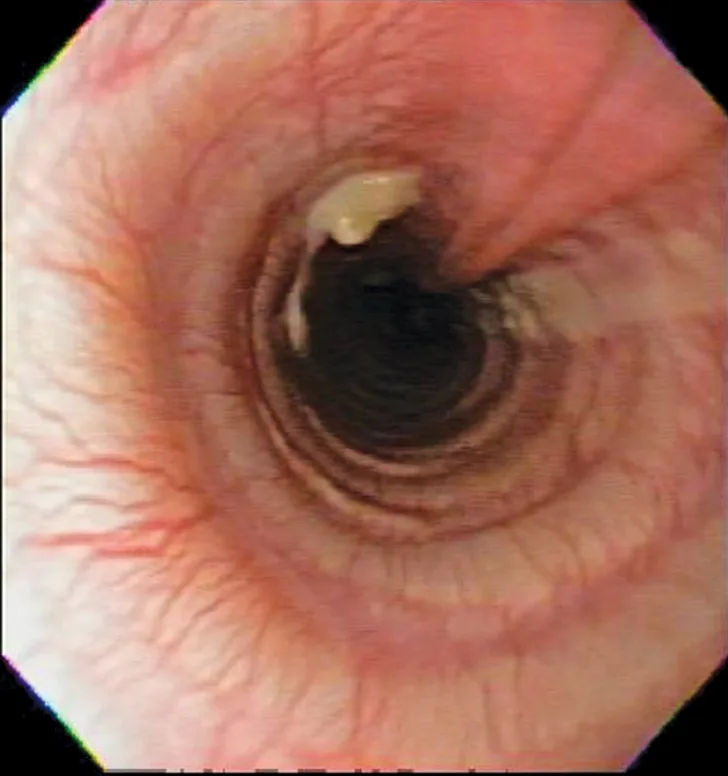

Bronchoscopic visualization revealed a moderate amount of thick, adherent, greenish-yellow mucus in the trachea and secondary and tertiary bronchi; mucosa was moderately irregular and erythematous (Figure 2). There was no evidence of airway collapse. Samples were collected via bronchoalveolar lavage for cytology, aerobic culture, and Mycoplasma spp culture.

Bronchoscopy results demonstrating mucosal irregularity, hyperemia, and characteristic greenish-yellow airway exudate

Cytologic evaluation of the airways confirms eosinophilic inflammation, which is the hallmark of diagnosis. The percentage of eosinophils (mean, 61% of the total nucleated cell population4) exceeds that of healthy dogs (5%-24%).2,5,10 Samples can be obtained via tracheal wash or bronchoscopy. Bronchoscopy allows for visualization of more characteristic airway associated changes (eg, greenish-yellow secretions, irregular mucosa, hyperemia).2,5,11 Occasionally, intraluminal granulomas may be present,4 allowing for mucosal brush samples or biopsies that can further support a diagnosis. Tracheal washes provide appropriate cytologic samples in most cases. Bronchoscopy is generally reserved for patients with more focal radiographic disease, concerns for neoplasia, or suspicion for concurrent structural disorders (eg, bronchial collapse, tracheal collapse).